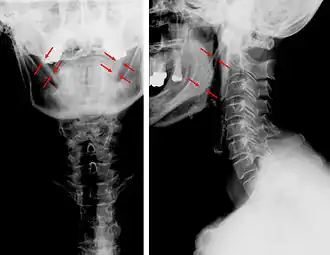

| Rx da coluna vertebral-ossificação bilateral dos ligamentos estilo-hióideos | |

A Síndrome de Eagle é um conjunto de sintomas e sinais resultante da ossificação ou aumento do ligamento estilo-hióideo secundário a uma hipertrofia da apófise estilóide do osso temporal. Pode originar dor facial, otalgia, cefaleias, disfagia, odinofagia, zumbidos e muitas vezes trismo (contratura espasmódica do músculo masseter). O diagnóstico da Síndrome de Eagle é difícil. Os sintomas descritos acabam por ser atribuídos a outras causas. Os exames radiológicos nem sempre são conclusivos, se não forem específicos (incidências especiais) para investigação desta patologia. Muitas vezes estes doentes são considerados com sofrendo de patologia psicossomática e são encaminhados ao psiquiatra.[1]

A calcificação do ligamento do estilo-hióideo causa limitação dos movimentos cervicais e dores intensas na região. É uma causa importante de nevralgia secundária do glossofaríngeo. Aparece sobretudo na idade adulta e no sexo feminino. É raro antes dos 30 anos.[2] O diagnóstico é eminentemente radiográfico. O tratamento nos casos menos graves é feito com analgésicos. Por vezes, o paciente tem que ser assistido em cirurgia maxilo-facial já que na maioria dos casos o tratamento médico é ineficaz.[3]